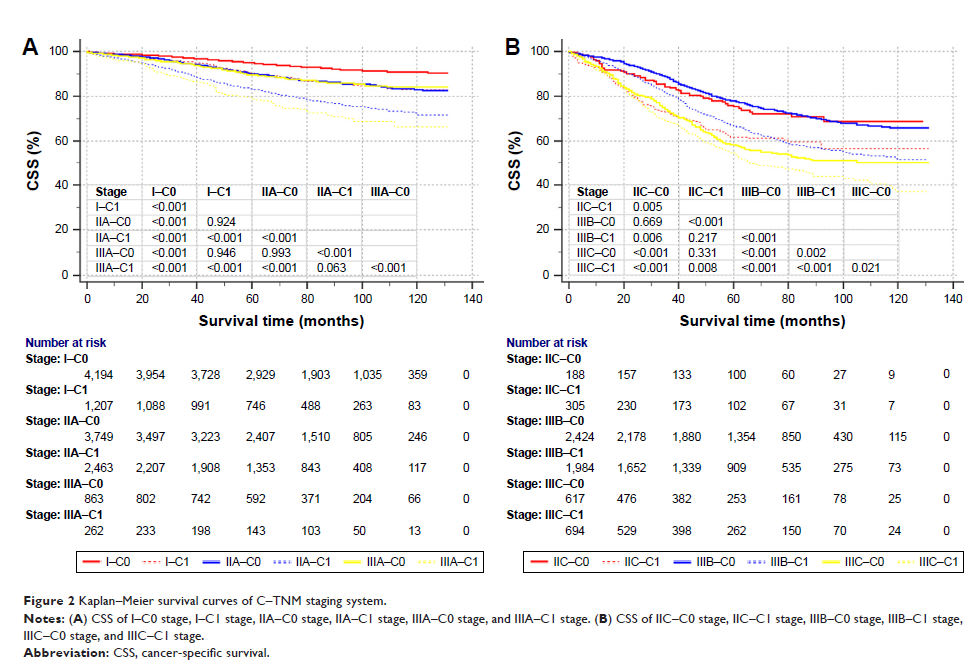

癌胚抗原与美国癌症联合委员会 TNM 分期系统在直肠癌中结合使用:一项现状调查和基于人群的大型研究

- 作者:Qi Liu, Peng Lian, Dakui Luo, Sanjun Cai, Qingguo Li, Xinxiang Li

- 期刊:OncoTargets and Therapy